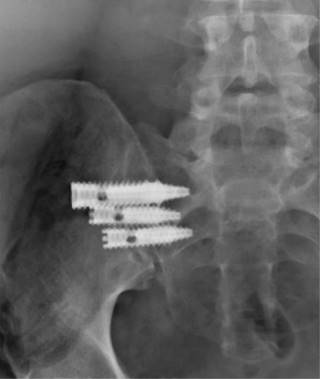

Las técnicas de cirugía mínimamente invasiva (Figura 9) han sido descritas con dos enfoques básicos, transarticular dorsal o lateral. Con el abordaje dorsal la articulación se distrae y se coloca un aloinjerto o un implante de fusión en la articulación. En la técnica lateral se colocan tornillos o jaulas empaquetadas con materiales de injerto o implantes metálicos triangulares a través de la unión para estabilizar.25,26 Los estudios biomecánicos han revelado que estos métodos reducen significativamente el movimiento de la articulación. Se han descrito varios tipos de implantes para la fusión dorsal sacroilíaca, incluyendo aloinjerto de espigas fibulares, autoinjerto de cresta ilíaca y jaulas de titanio con injerto. En la mayoría de los casos, la fusión de la articulación se logra por medio de la técnica transarticular lateral utilizando implantes huecos en forma de tornillo empaquetados con injerto, dos injertos combinados con injerto óseo empaquetado en la articulación o dispositivos triangulares de titanio.25,26,27,28